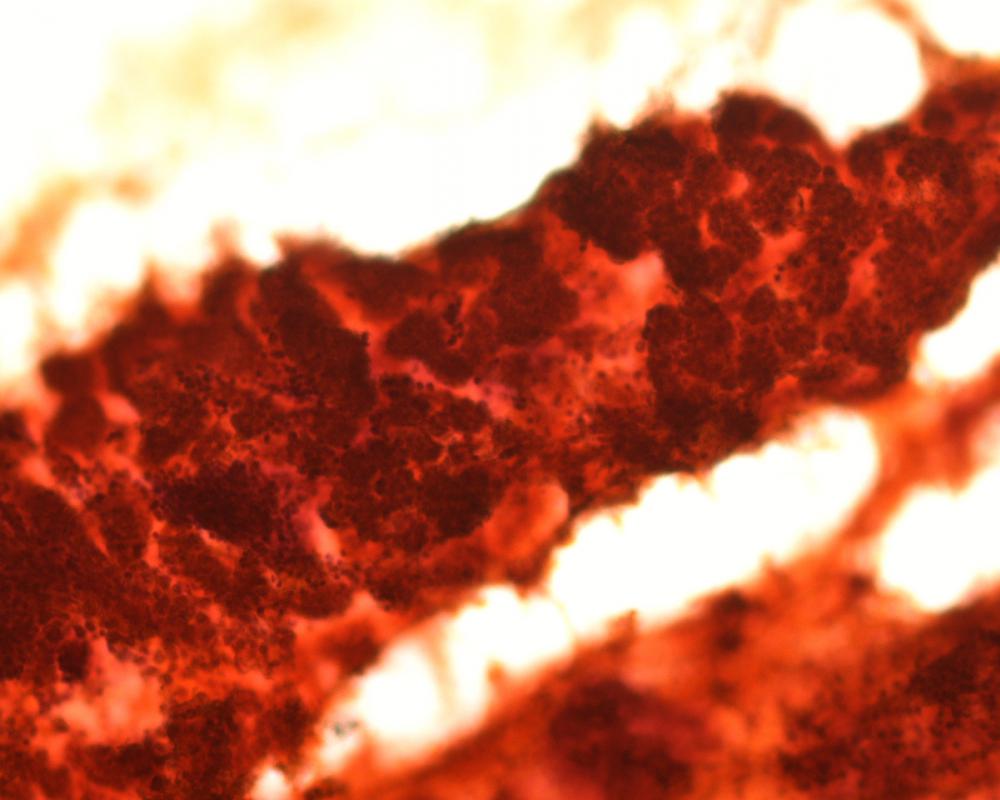

第34回日本臨床細胞学会九州連合会学会(長崎)スライドカンファレンス症例3

種別:泌尿器

出題:社会医療法人白十字会白十字病院 臨床検査科 大谷 博 先生

| 年齢 | 83歳 | 性別 | 男性 |

| 採取部位 | 左上部尿路 | 採取方法 | 左分腎尿 |

| 検体処理法 | LBC法(サイトリッチレッド, BD) |

既往歴:特記すべきことなし

現病歴:3か月前より肉眼的血尿が出現した。膀胱鏡にて膀胱後壁に径6 mmの単発性乳頭状腫瘍がみられたが,自然尿細胞診は陰性と診断された。CTにて左水腎症があり,下部尿管腫瘍が疑われたため左分腎尿が採取された。

| 正解 | 3.低異型度尿路上皮癌 |

| 1.尿路結石症 | 7件 | (7.2%) | |

| 2.内反性尿路上皮乳頭腫 | 40件 | (41.2%) | |

| 3.低異型度尿路上皮癌 | 39件 | (40.2%) | |

| 4.高異型度尿路上皮癌 | 1件 | (1.0%) | |

| 5.微小乳頭型浸潤性尿路上皮癌 | 10件 | (10.3%) | |

| 投票総数 | 97件 | (100%) |